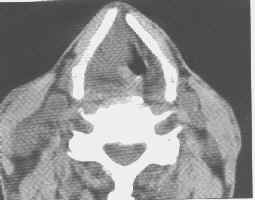

喉癌(CT平扫)

喉癌。CT平扫示右侧声门区有一较大的结节状软组织肿块,其密度较均匀,向前上外累及声带前联合和右侧梨状隐窝,致使其变形、闭塞、并波及右侧甲状软骨,引起该骨溶骨性破坏。右侧颈动脉鞘后方的淋巴结肿大,可见低密度区。